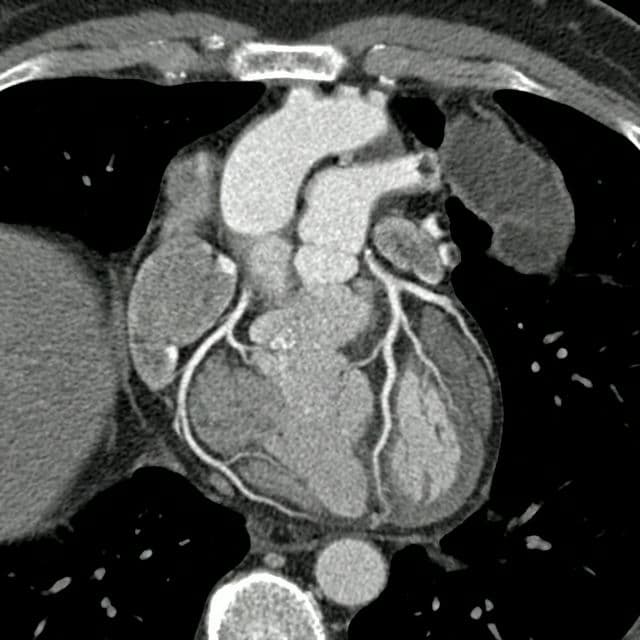

Negative — NormalROUTINE

Input — CT Coronary Angiogram

CT CORONARY ANGIOGRAM✓ NORMAL

CARD-2026-0213-N01MedVision AI v3.2

| Impression | “Normal cardiac CT angiogram with no evidence of coronary artery disease, left ventricular hypertrophy, or other structural abnormality. Entirely reassuring examination.” |

| Performance | Confidence: 9/10 · Analysis: 2.1s · Agreement: 96% |

| Remarks | This cardiac CT angiogram demonstrates entirely normal coronary artery anatomy with no evidence of atherosclerotic disease. Left ventricular function and morphology are normal. No additional cardiac or great vessel abnormalities identified. |

Findings (8)

Normal coronary artery anatomy with no stenosis or plaque

Coronary artery calcium score: 0 (no calcification)

Patent left main, LAD, LCx, and RCA without stenosis

Normal left ventricular wall thickness (9mm septal)

Preserved left ventricular ejection fraction (60-65%)

No pericardial effusion

Normal ascending aorta diameter (3.2cm)

No mediastinal lymphadenopathy